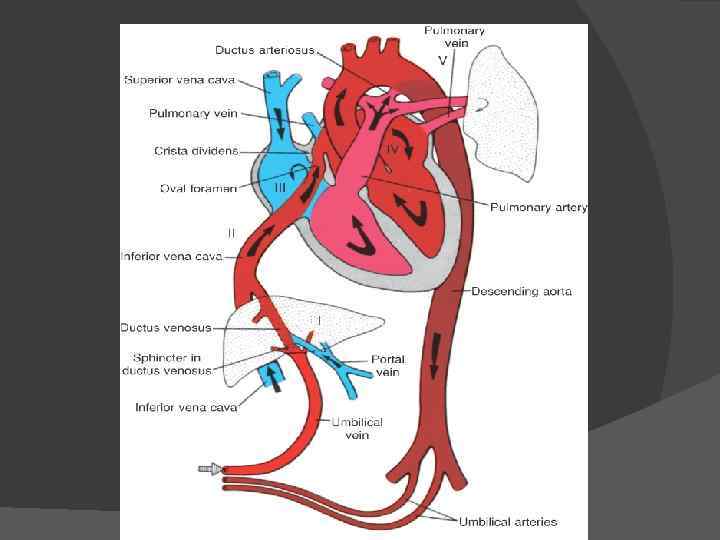

Пренатальный период Во внутриутробном периоде основная масса крови, поступающая из правого предсердия в правый желудочек и легочную артерию, попадает не в легкие, а через артериальный проток в аорту.

После рождения артериальный проток облитерируется. Это связано с тем, что изменяется соотношение органов средостения и при расширении легких проток, натянутый между легочной артерией и аортой, перегибается. Кроме того, на закрытие артериального протока влияет изменение химического состава крови.